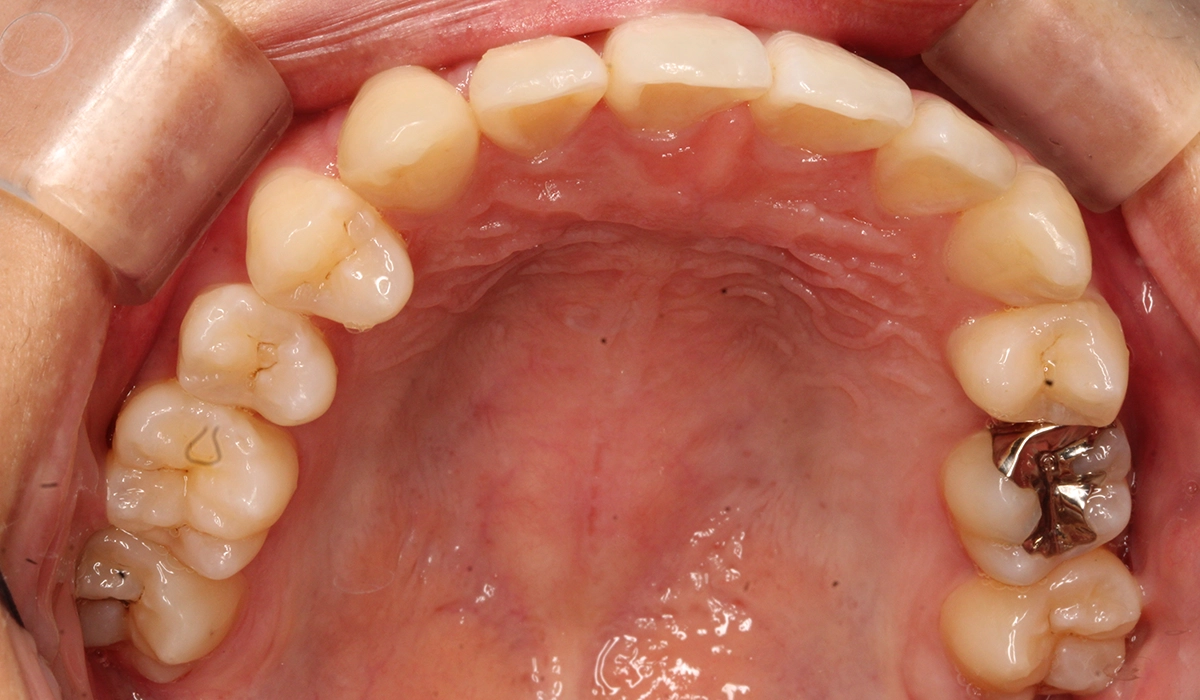

術前:下顎

術後:下顎